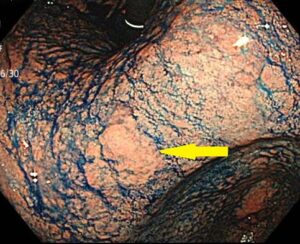

胃カメラでは、通常食道の全体・胃の内部・十二指腸の一部を観察します。

当院では鎮静剤を使用することで、反射を抑えながら咽頭(のどの奥)の観察も可能です。

胃カメラでわかるがんには、咽頭がん・食道がん・胃がん・十二指腸がんがあります。

胃カメラ(上部消化管内視鏡):口または鼻から細いカメラを入れて、食道・胃・十二指腸の内側を直接観察する検査。

咽頭:口の奥〜喉の入口にあたる部位で、胃カメラで観察できることがある。

食道:咽頭と胃をつなぐ管状臓器で、胃カメラで全体を観察する。

胃:食物をためて消化を始める袋状の臓器で、内腔を隅々まで観察する。

十二指腸:胃の出口に続く小腸の最初の部分で、胃カメラで一部を観察する。